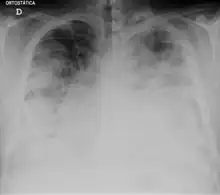

Chest X-ray of a severe case of legionellosis upon admission to the emergency department

Laboratory tests may show that kidney functions, liver functions, and electrolyte levels are abnormal, which may include low sodium in the blood. Chest X-rays often show pneumonia with consolidation in the bottom portion of both lungs. Distinguishing Legionnaires' disease from other types of pneumonia by symptoms or radiologic findings alone is difficult; other tests are required for definitive diagnosis.